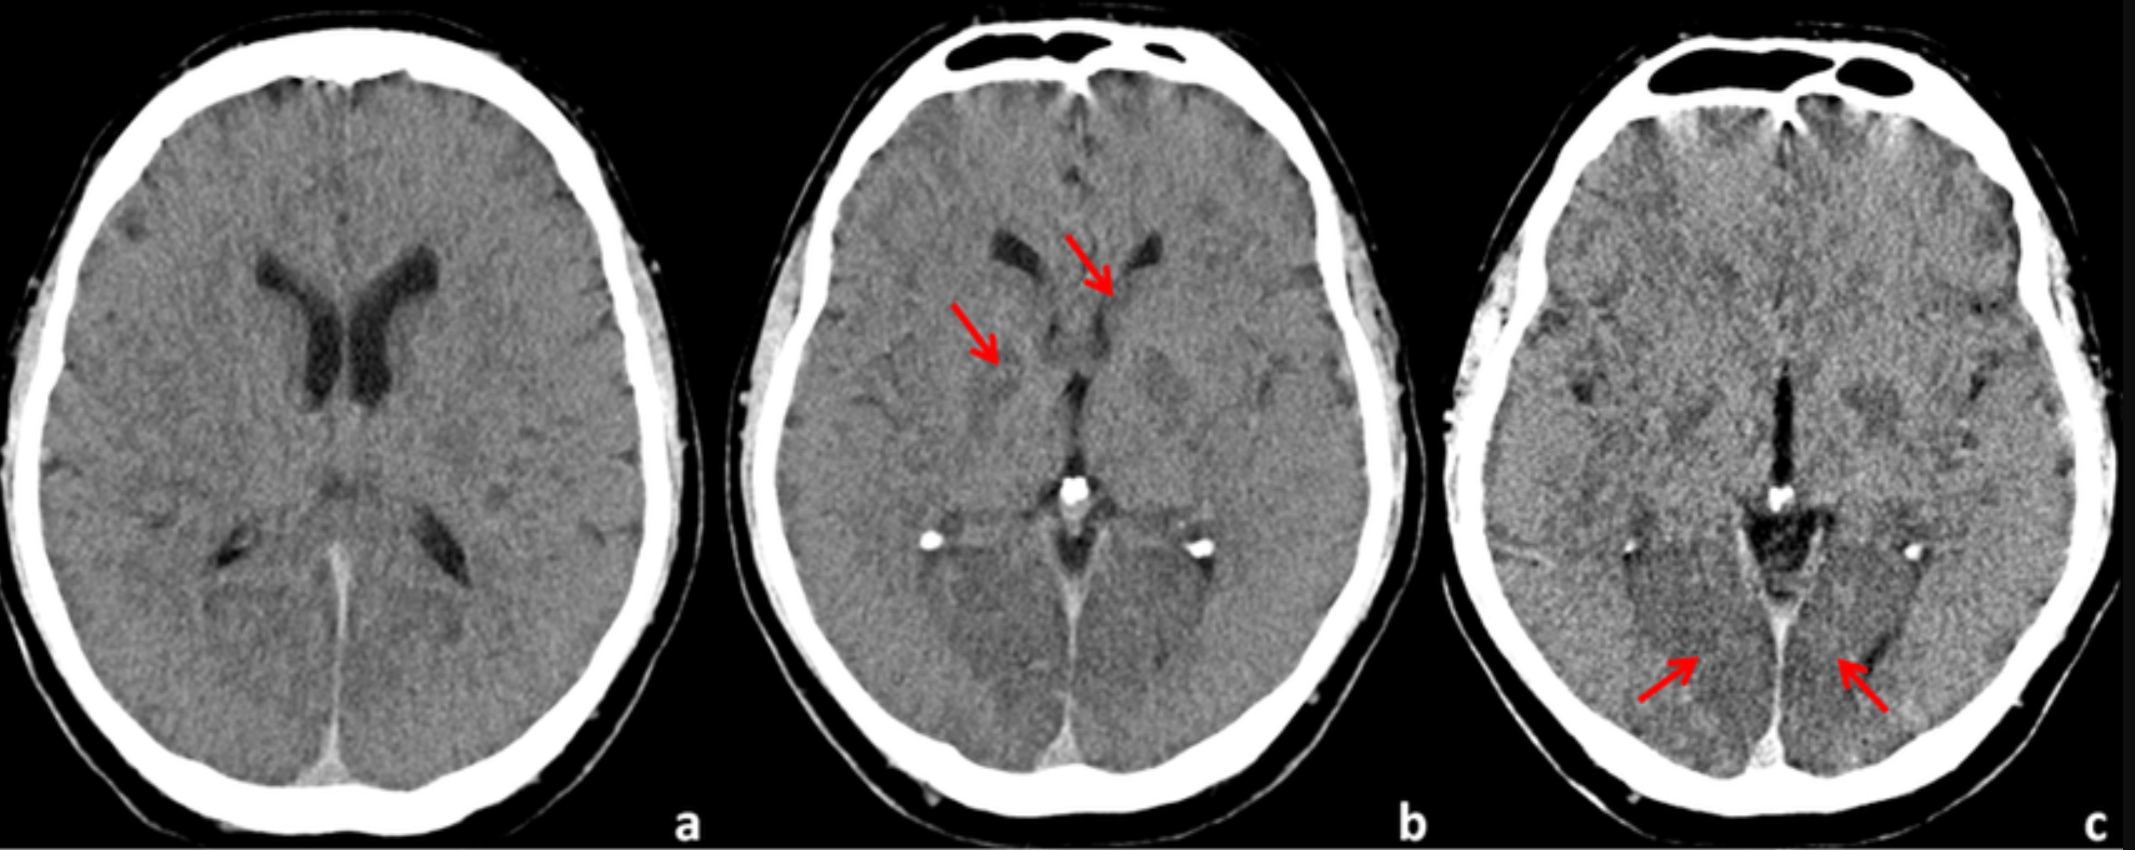

豆状核模糊

正常状态下,通过 CT 能够清晰观察到三角形状的豆状核,以及其内侧的内囊膝部、前后支,外侧低密度的外囊和岛叶皮层。然而,一旦发生脑梗死,豆状核边缘会变得模糊,内外囊与豆状核的分界不再清晰,岛叶皮层也可能出现肿胀的低密度影。